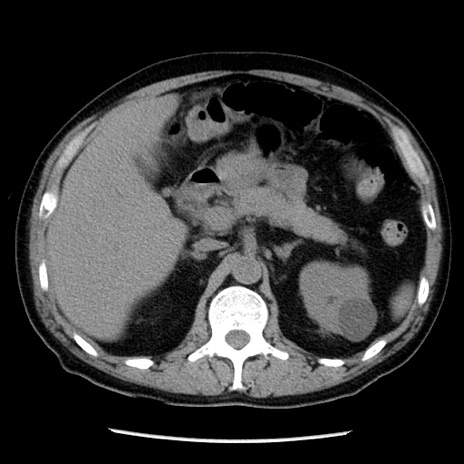

症例29(横断像)

【症例】40歳代男性

【現病歴】2日前から胃痛あり。徐々に周期的な激痛に変化した。本日になっても激痛があるため受診。

【身体所見】意識清明、BT 38-39℃台あり、腹部:膨満、やや硬、右下腹部に圧痛あり。

【データ】WBC 8500、CRP 23.26